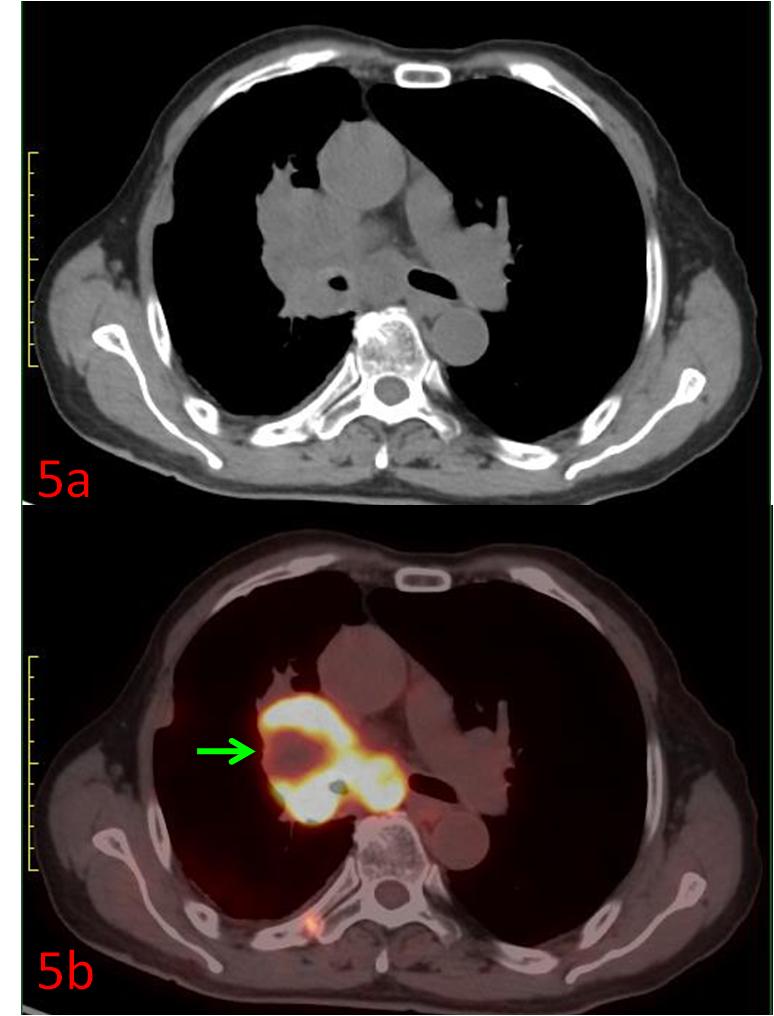

例5:中年女性,右肺上葉小細胞癌,CT示右肺門腫塊(圖5a),PET/CT展示了腫瘤內部代謝的不均質,中心區(qū)域存在部分壞死組織(圖5b綠箭),為放療計劃制定提供更準確信息。